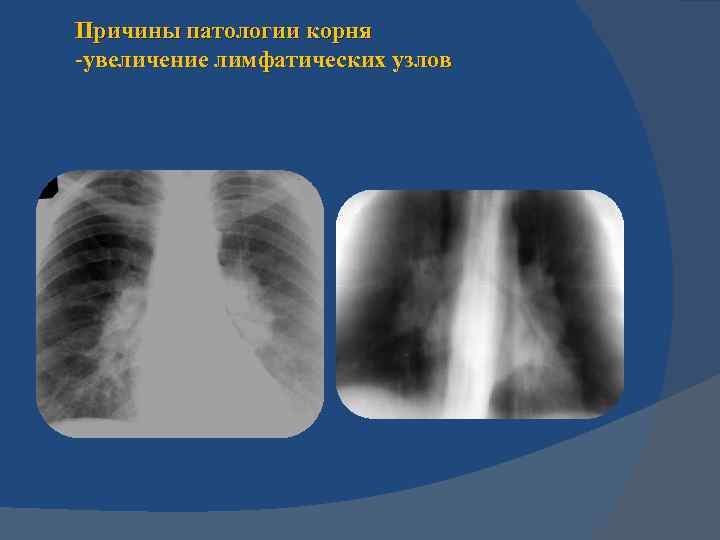

Синдром патологии корня легкого неструктурность и расширение корня легкого Причины патологии корня -увеличение лимфатических узлов – лимфаденопатия, -нарушение гемодинамики – -ЛВГ и ЛАГ

Синдром патологии корня легкого неструктурность и расширение корня легкого Причины патологии корня -увеличение лимфатических узлов – лимфаденопатия, - нарушение гемодинамики – ЛВГ и ЛАГ

Причины патологии корня -увеличение лимфатических узлов